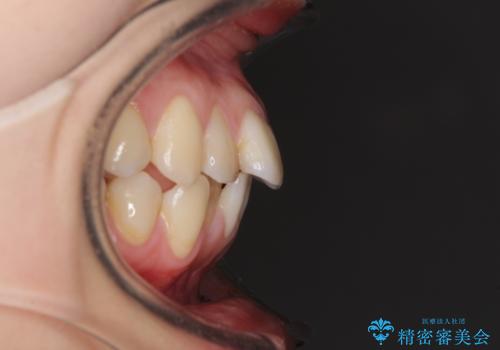

- 上下前歯のデコボコを気にして来院された患者様です。

インビザラインによる上下歯列の側方拡大と後方移動、IPR(歯と歯の間を削る)にるスペースの獲得により歯列を整えることとしました。